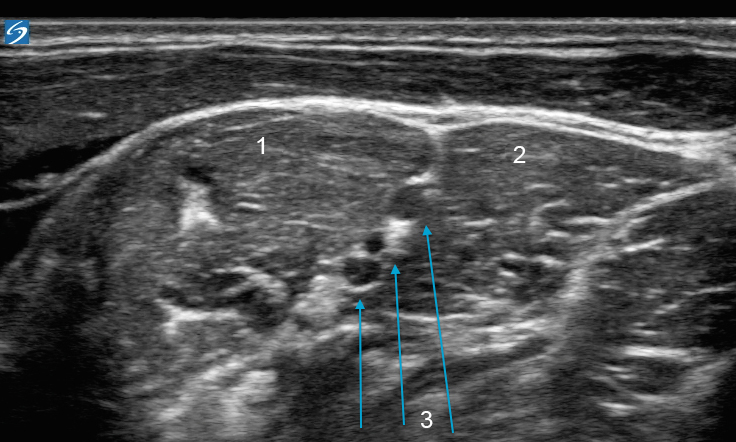

X-Porte: 斜角筋間神経画像

前斜角筋

不等辺内側

神経束